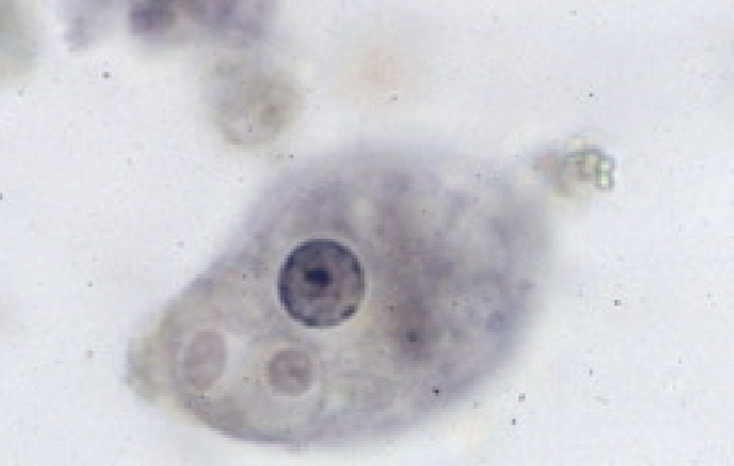

Entamoeba histolytica (troph)

Entamoeba histolytica (troph)